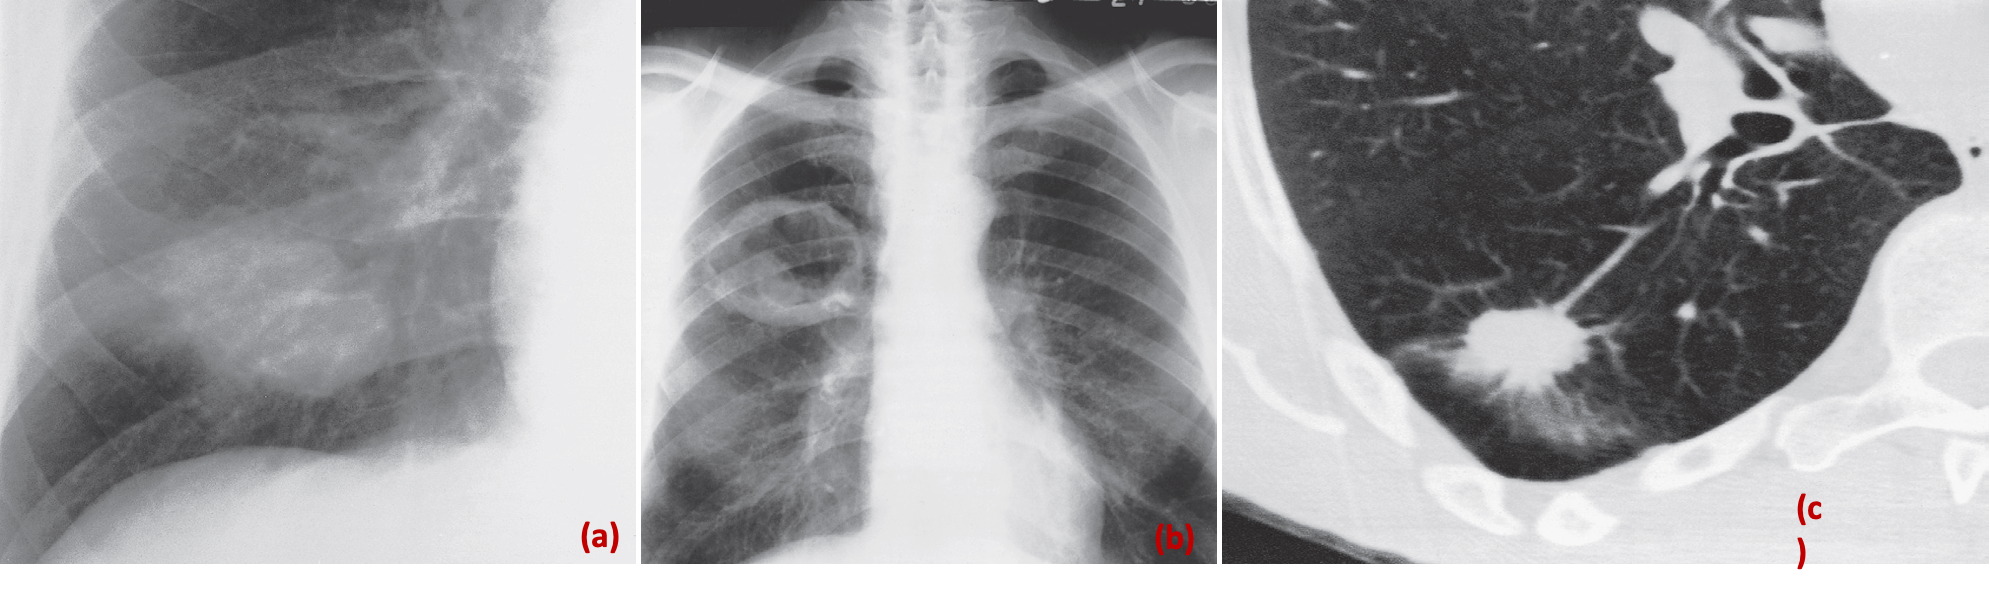

- Appearance of peripheral lung carcinoma. A lobulated mass (a) - opacity – calcified lesion

- **Cavitating mass (b) are shown on plain films.

- **A spiculated mass (c) is shown on CT